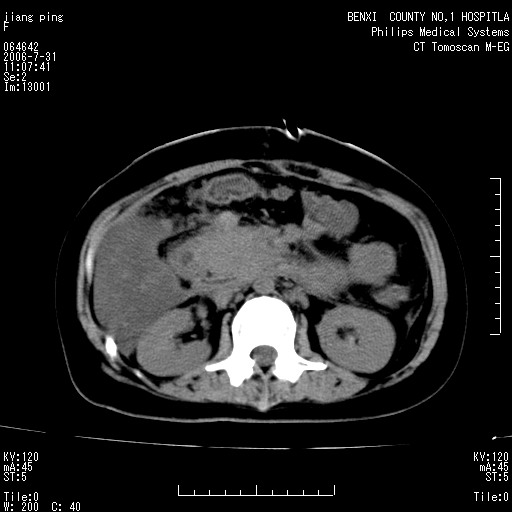

以下是引用jiajie在2006-7-31 20:34:00的发言:[br]支持营养不良导致脂肪肝。[br]胰头增大界限不清,考虑为胰腺炎破坏十二指肠粘膜、肠壁增厚、肠腔狭窄,并与胰头粘连所致。